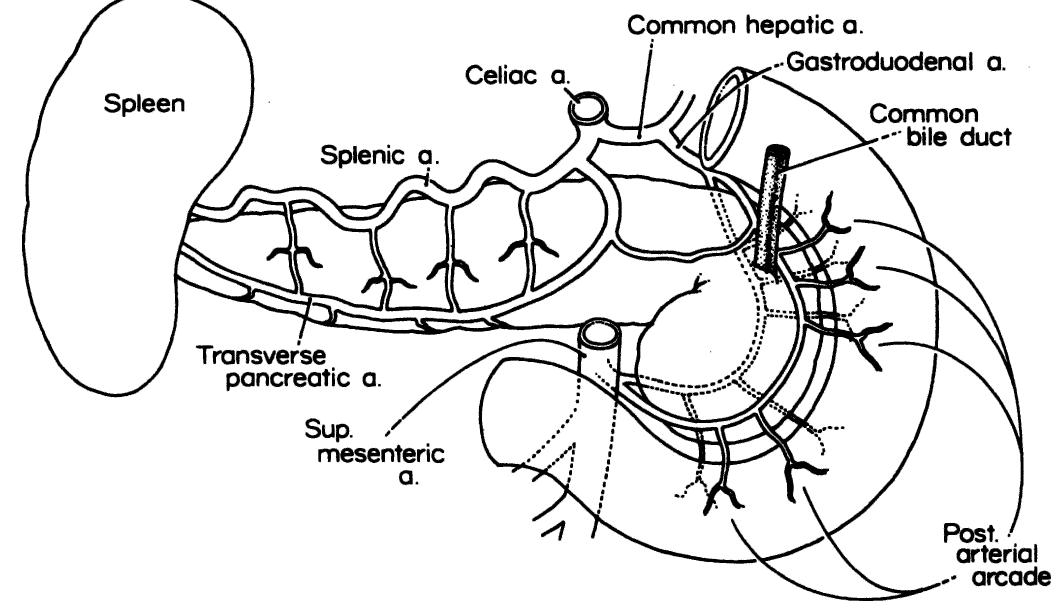

- The ligament contains the following structures: left gastric artery and vein; hepatic division of left vagus trunk; lymph nodes; occasionally, both vagal trunks; occasionally, branches of the right gastric artery and vein; the left hepatic artery when it arises from the left gastric artery (in 23 percent of cases).

- The portal vein lies behind the pancreas and in front of the inferior vena cava, with the common bile duct on the right and the common hepatic artery on the left.

- In this ligament, the proper hepatic artery lies to the left of the common bile and hepatic ducts and anterior to the portal vein.